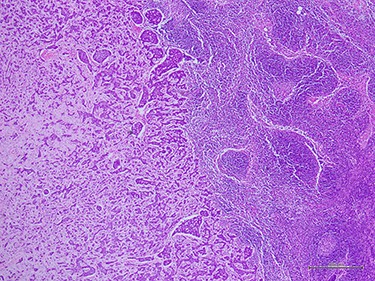

(A) Histologic examination showed the neoplastic cells predominantly arranged in a solid growth pattern (100×). (B) The true glandular spaces lined by luminal-type epithelial cells (600×). (C) The pseudolumens containing watery basophilic mucopolysaccharides basement membrane-like materials rimmed myoepithelial cells (400×). (D) Intraductal components composed of a dual population as the invasive areas (600×)

complex. The left axillary lymph node was found to measure 1 cm after palpation. A mammogram revealed an ill-defined mass at sub-areolar on left breast with angulation 2.3 × 1.9 cm, without suspicious microcalcification or architectural distortion (Fig. 1). Core needle biopsy revealed invasive ductal carcinoma (IDC). Immunohistochemical study (IHC) showed Estrogen receptor (ER), Progesterone receptor (PR), and Human epidermal growth factor receptor 2 (HER2) negative. Fine needle aspiration of left axillary lymph node revealed poorly differentiated metastatic lymph nodes. Metastatic workups were unremarkable. Left lumpectomy and axillary lymph nodes dissection were performed. The final pathology reported ACC measuring 3.5 cm in greatest dimension, lymphovascular invasion, presenting with DCIS, comedonecrosis type, high grade nuclei, microcalcification, all margins are negative for malignancy (Fig. 2). IHC showed CD117 and CK7 positive for malignant ductal cell of tumor, CK5/6 and p63 positive for myoepithelial cells within the tumor. ER, PR and HER-2 were negative. Ki-67 was strongly positive 3 + of nuclear staining, 30% of neoplastic cells (Fig. 3). One of 21 lymph nodes demonstrated metastatic ACC with extranodal extension (Fig. 4). Metastatic part is 0.9 cm in greatest dimension. Postoperative adjuvant chemoradiotherapy was given.